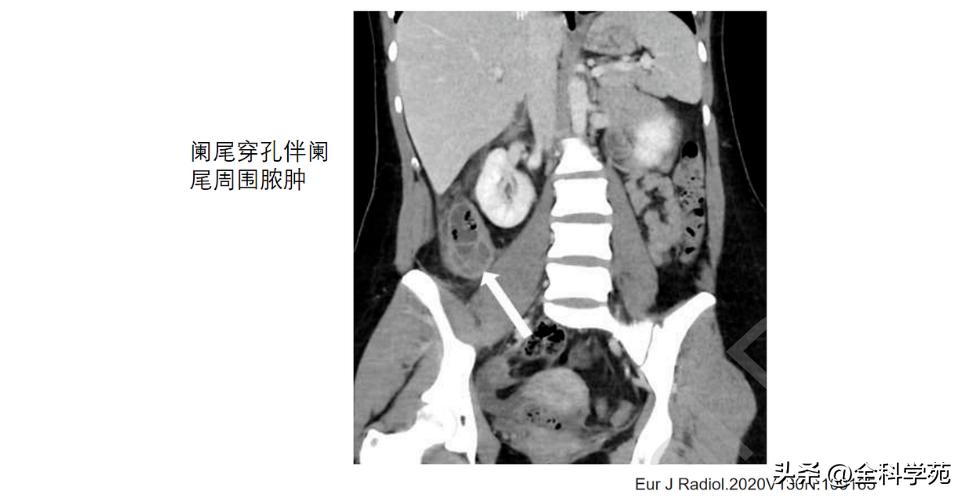

◆ 穿孔 (Perforation)

◆ 局部低强化是穿孔征象

◆ 蜂窝织炎和脓肿 (Phlegmon and abscess